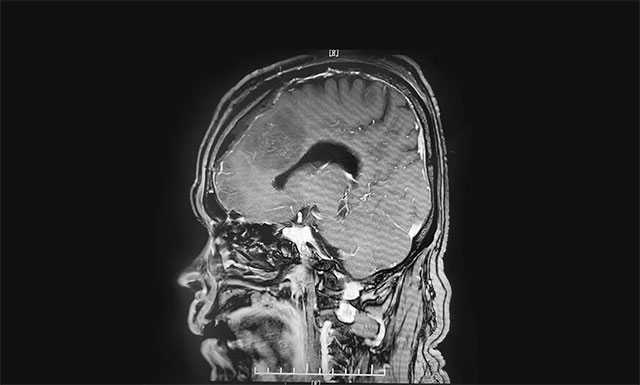

▲ 術(shù)后影像顯示腫瘤被切除

術(shù)中可見腫瘤起源于大腦鐮并跨越兩側(cè),在顯微鏡下,李士其教授在吳治群博士、黃秀夫醫(yī)生及醫(yī)護(hù)團(tuán)隊協(xié)助下,憑借精湛的手術(shù)技巧和豐富的臨床經(jīng)驗(yàn)對腫瘤進(jìn)行精細(xì)剝離。在充分保護(hù)好上矢狀竇、中央?yún)^(qū)的靜脈回流的前提下,經(jīng)過5個多小時的手術(shù),最終腫瘤被順利切除。術(shù)后的病理結(jié)果顯示是良性腦膜瘤。